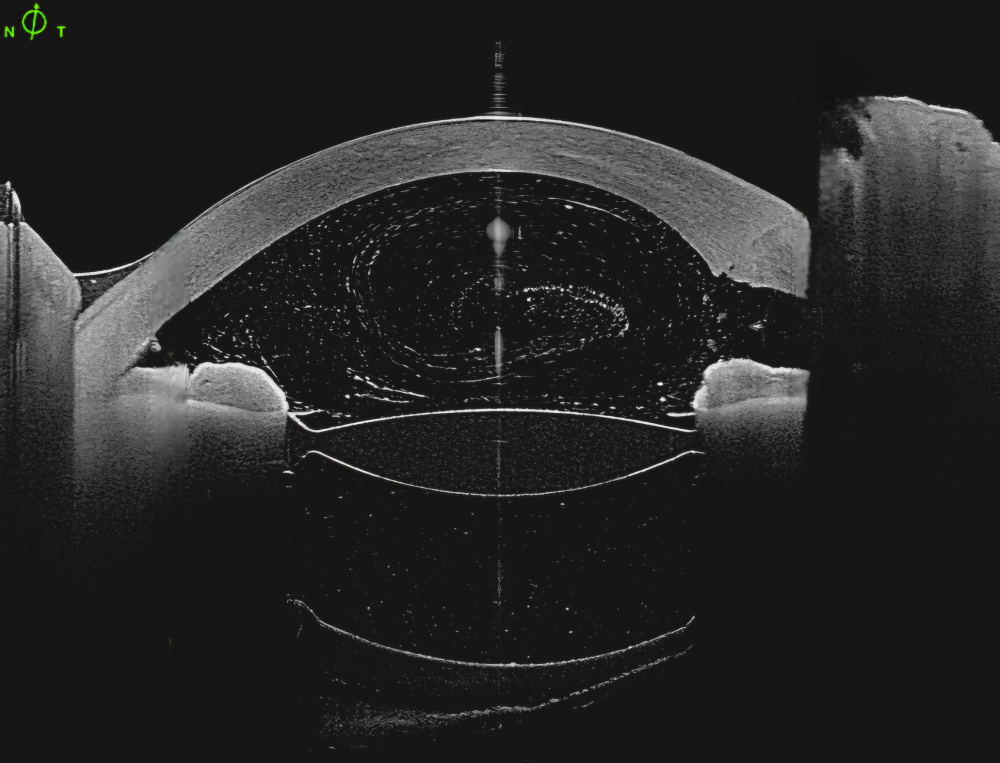

Título: Eye Of The Storm

Autor: João Castro Cabanas

Coautores: JDaniel Cardoso, Pedro Moreira Martins, Ricardo Machado Soares

Instituição: Unidade Local de Saúde Gaia e Espinho

Descrição: AS-OCT image of an eye diagnosed with early postoperative capsular block syndrome immediately after Nd:YAG anterior capsulotomy